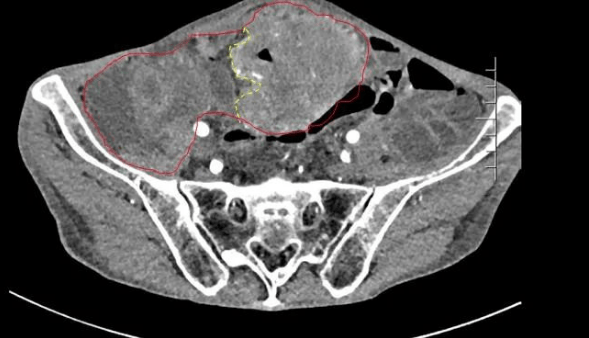

患者王大爺,男,72歲,發(fā)現(xiàn)腹腔腫物10余年,近兩年來患者雙下肢乏力、貧血,依靠間斷輸血維持著正常生活,出現(xiàn)頭昏,行動(dòng)困難,腹部疼痛及便血慕名來我院就診。入院后查體評(píng)估患者年齡大,體質(zhì)差,嚴(yán)重貧血,肺部感染及腸梗阻征象,腹部增強(qiáng)CT檢查提示腹膜后巨大腫瘤,長徑超過30厘米,占據(jù)大部分腹腔,并可能存在雙原發(fā)腫瘤。

苗滿園腫瘤外科團(tuán)隊(duì)在麻醉科/手術(shù)室的緊密配合下為該患者進(jìn)行手術(shù),術(shù)中發(fā)現(xiàn)腫瘤巨大,幾乎占據(jù)了整個(gè)腹腔,從左側(cè)向右腹腔延伸,向上將肝、腎擠向膈下,向左將胃及小腸擠向左上腹,向下深達(dá)盆腔內(nèi),包繞下腔靜脈、腸系膜上動(dòng)脈等大血管及輸尿管,回盲部及回腸也受侵犯。手術(shù)難度巨大,風(fēng)險(xiǎn)極高。團(tuán)隊(duì)?wèi){借著高超的手術(shù)技能和精準(zhǔn)的手術(shù)預(yù)案沉著應(yīng)對(duì),迎難而上,應(yīng)用高頻電刀、超聲刀、切割縫合器等先進(jìn)設(shè)備,耗時(shí)近5小時(shí)為患者切除了巨大腹腔腫瘤,并聯(lián)合右半結(jié)腸切除,術(shù)中出血僅50ml。術(shù)后病理為腹膜后巨大平滑肌瘤+回腸腺癌。